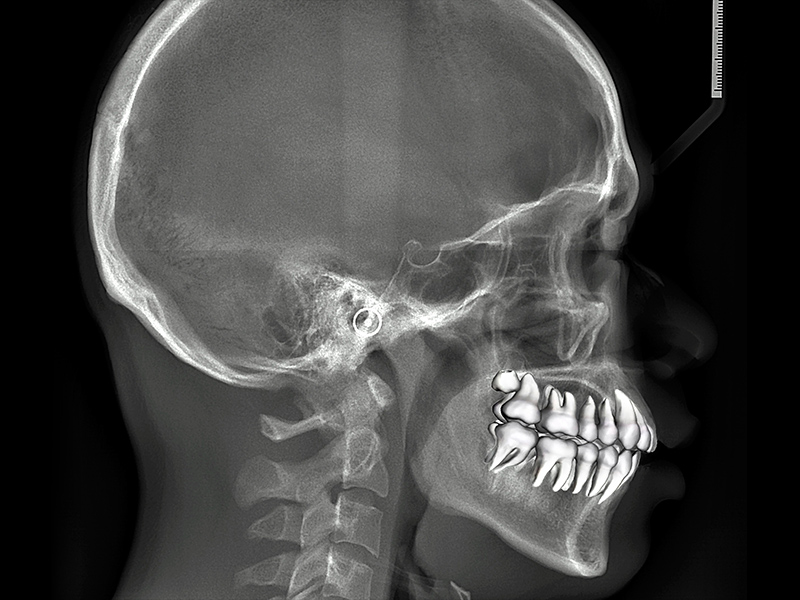

투명교정은 정교함이 핵심 POINT! 수치과병원은 “치과용 고정밀 3D프린터, 3D스캐너”를 사용하여 치아를 정밀 스캔하여 정확도와 예측성을 높입니다.